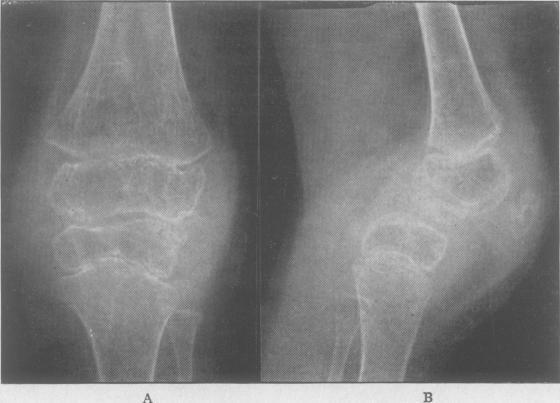

Juvenile rheumatoid arthritis (Still's disease).